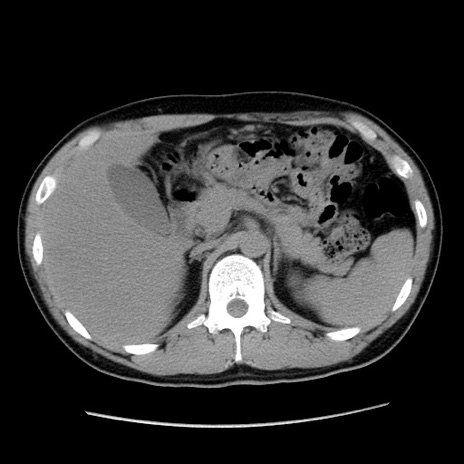

症例36(横断像)

【症例】20歳代 男性

【主訴】心窩部痛

【現病歴】今朝より上腹部痛あり。一旦軽快していたが再度出現したため救急要請。昨日夕に白身の魚を含む刺身を食べた。

【身体所見】BP 136/89mmHg、HR 74/min、BT 37.0℃、腹部:膨満、軟、心窩部に圧痛あり。反跳痛なし、筋性防御なし、腸雑音やや亢進あり。

【データ】WBC 17700、CRP 0.48